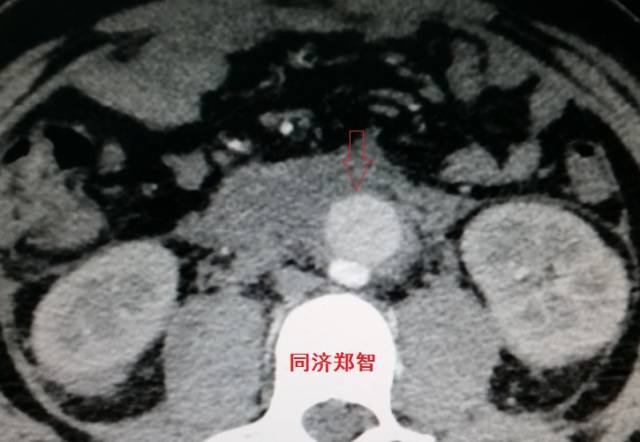

腹主动脉平扫CT提示正常外周一圈的钙化影中有内移的钙化影(红色箭头所示),CTA 证实为腹主动脉夹层

图19-20